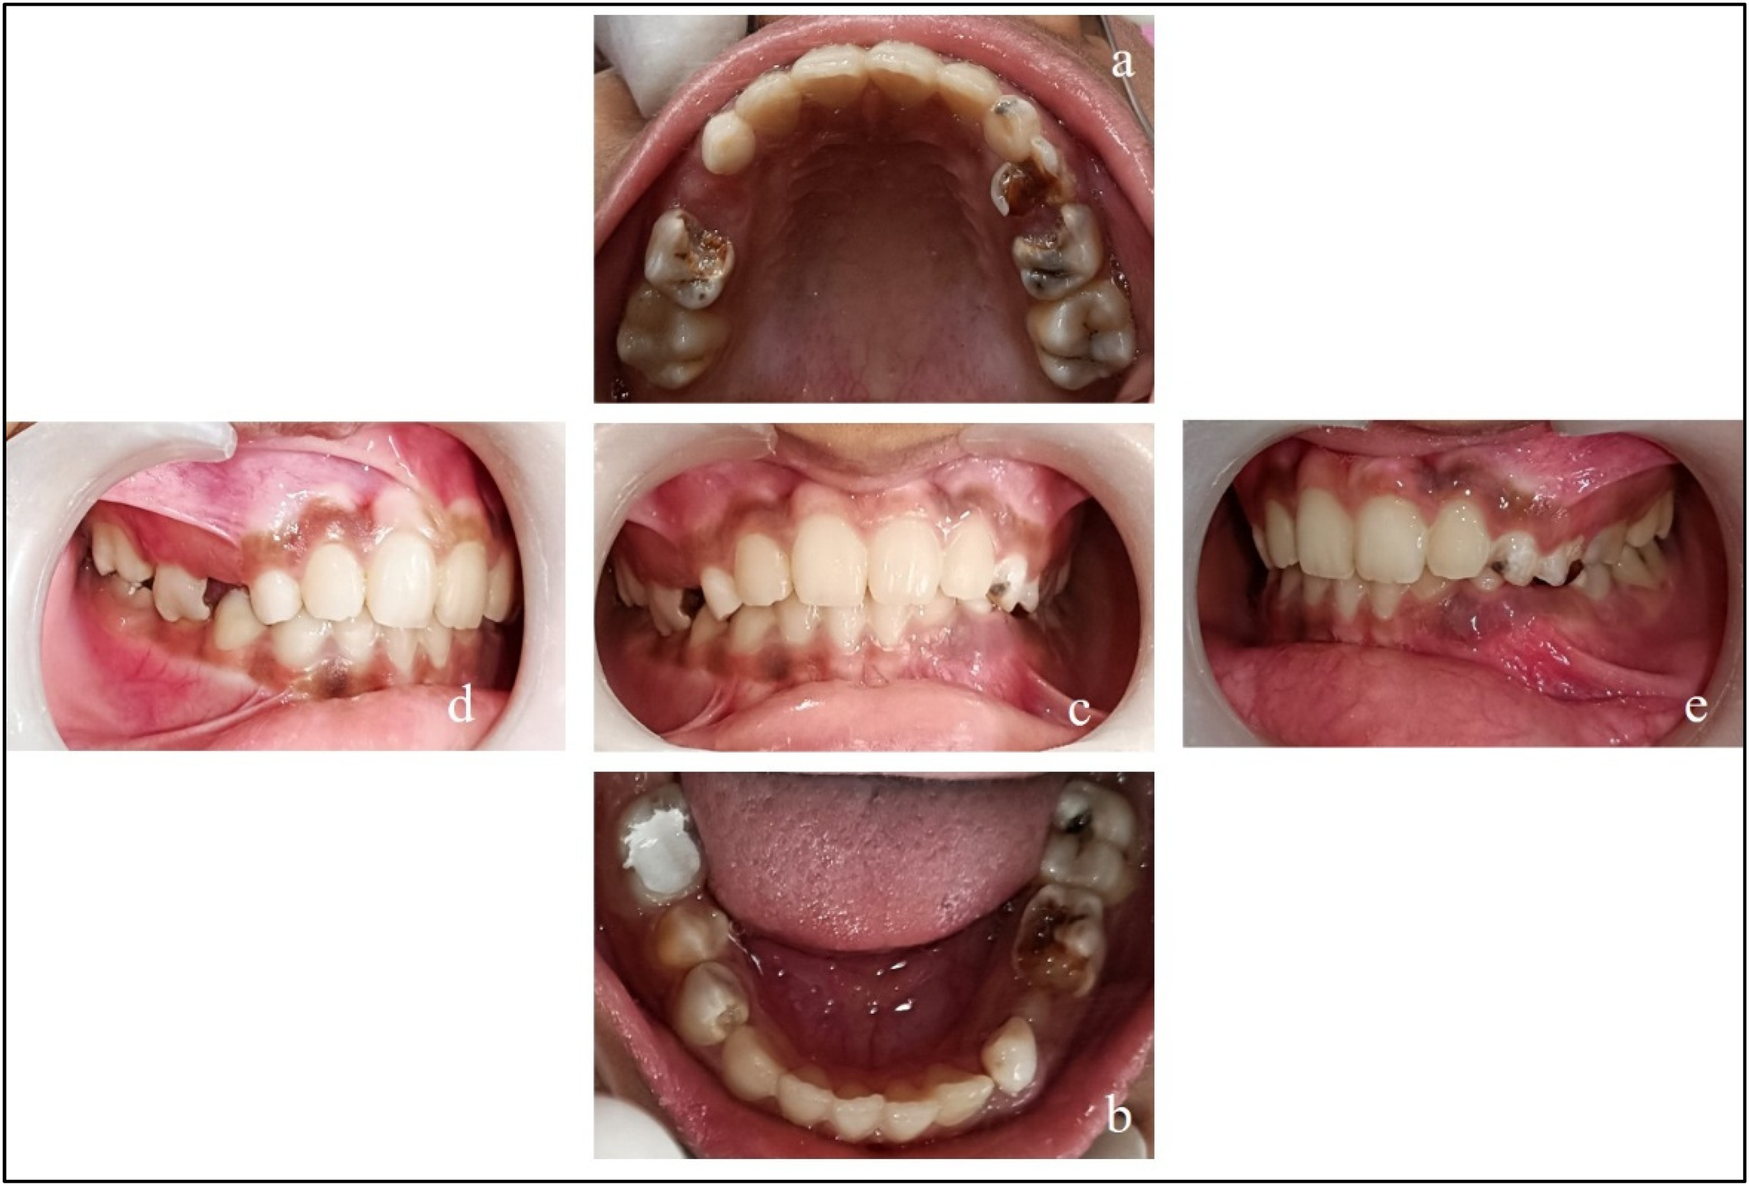

All the teeth in this report have been named as per Federation Dentaire Internationale (FDI) system. On clinical examination (Figure 1), the teeth present were 16, 55, ^14, 53, 12, 11, 21, 22, 63, 64, 65, and 26 in the upper arch and 46, ^45, ^44, 83, 42, 41, 31, 32, 73, ^34, 75, and 36 in the lower arch.

Figure 3. Pre-treatment records. (a) Maxillary arch; (b) mandibular arch; (c) at occlusion; (d) right lateral occlusion; and (e) left lateral occlusion.